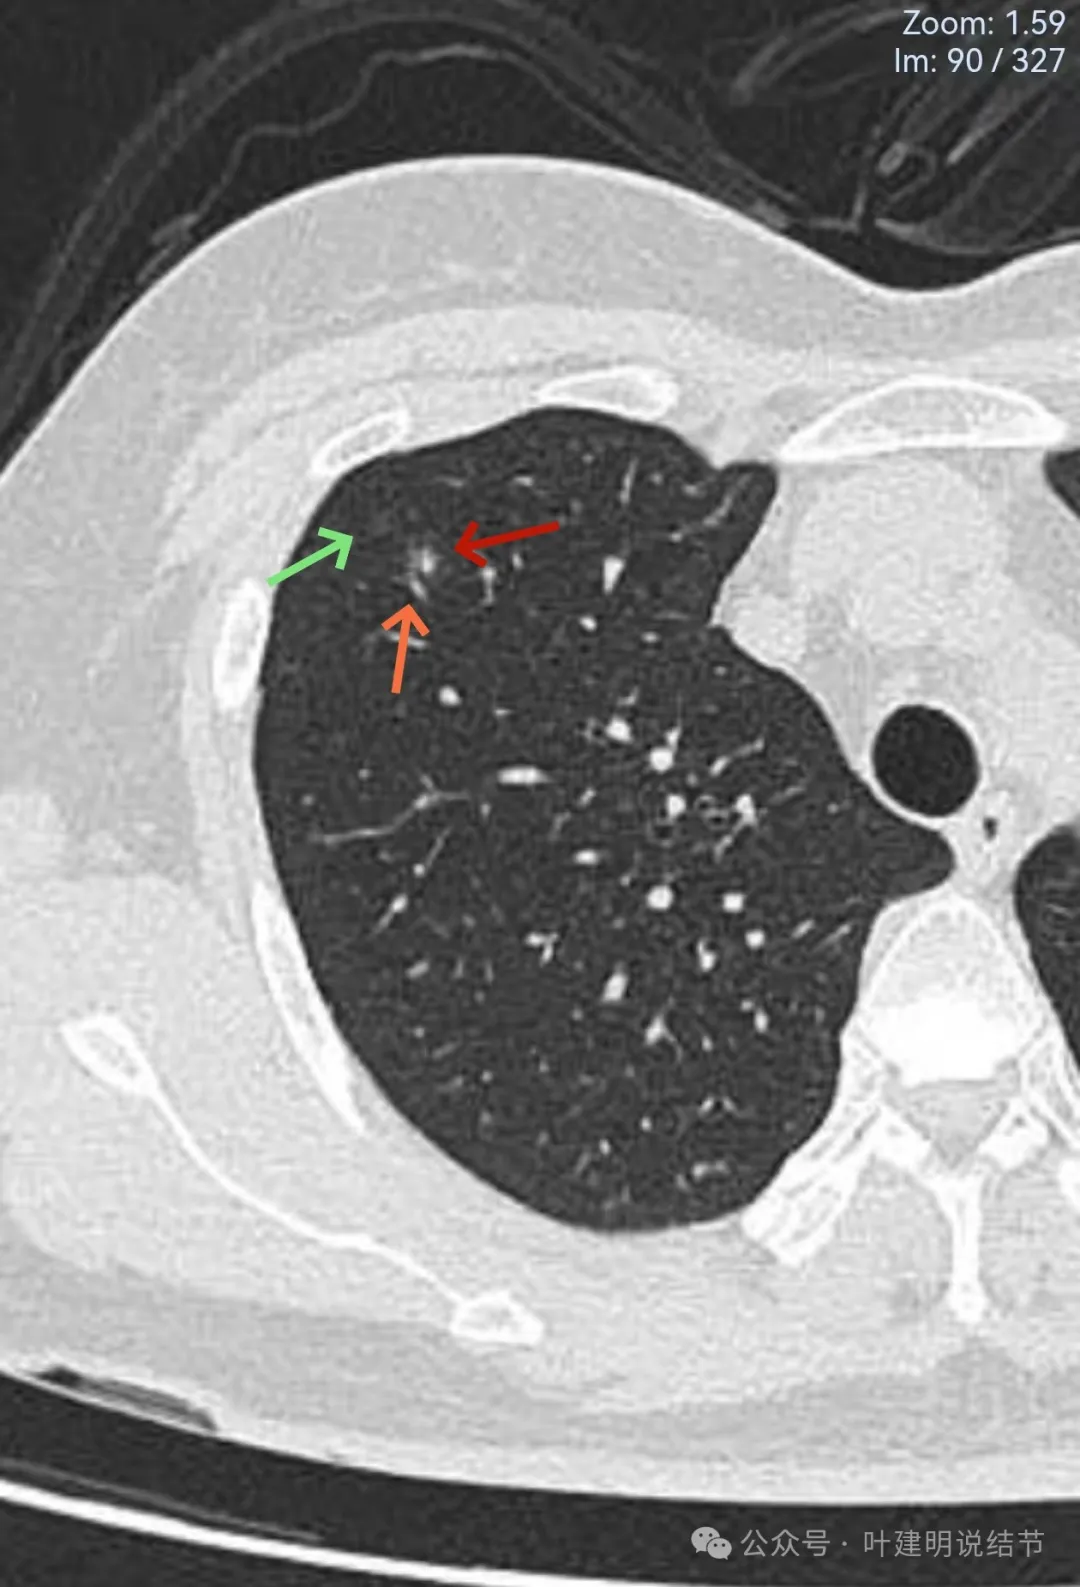

病灶出现,轮廓不清,边缘显糊。

有细支气管通气征,沿扩张的细支气管两侧有密度较高的阴影,再外围有淡的边界不清的磨玻璃成分。

有血管经过病灶处,但距离这么近,血管却没有被影响或形成血管弯。绿色箭头处距病灶有一定距离,但也有淡而模糊的磨玻璃影。

病灶附近多发微小空泡样结构(砖色箭头),病灶边缘轮廓不清(如天蓝色箭头所示),病灶内部有实性密度伴空泡征的结节。

绿色箭头所示的磨玻璃影与主病灶并不相连的;主病灶轮廓不清;附近许多小空泡样结构;血管没有异常增粗或进入病灶内。